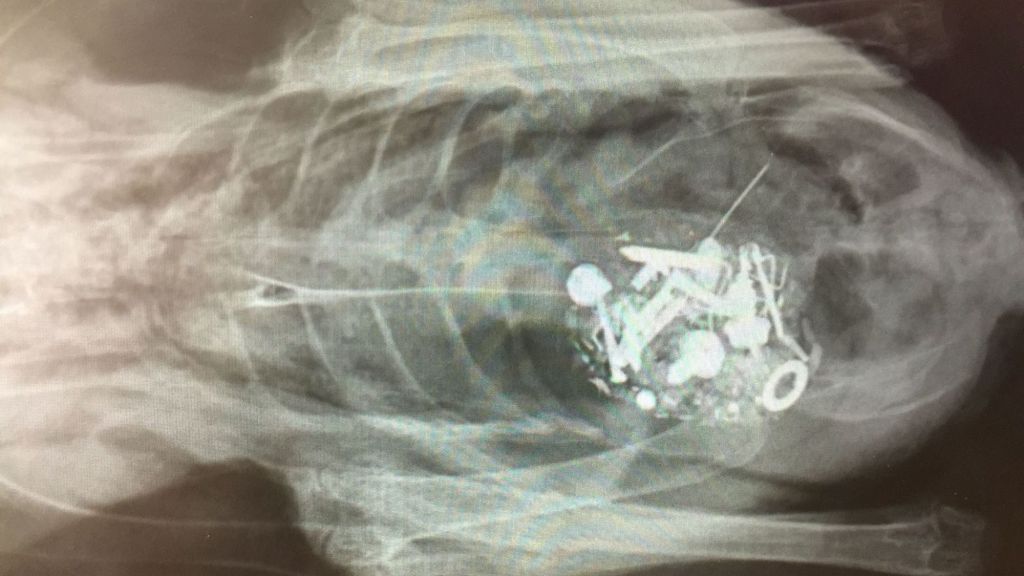

Several years ago I had a much loved poodle, Simon, who had a penchant for eating things that got stuckContinue Reading

Zinc Toxicity Chickens explore their world beak first and often peck at things that aren’t edible or healthy. If theyContinue Reading